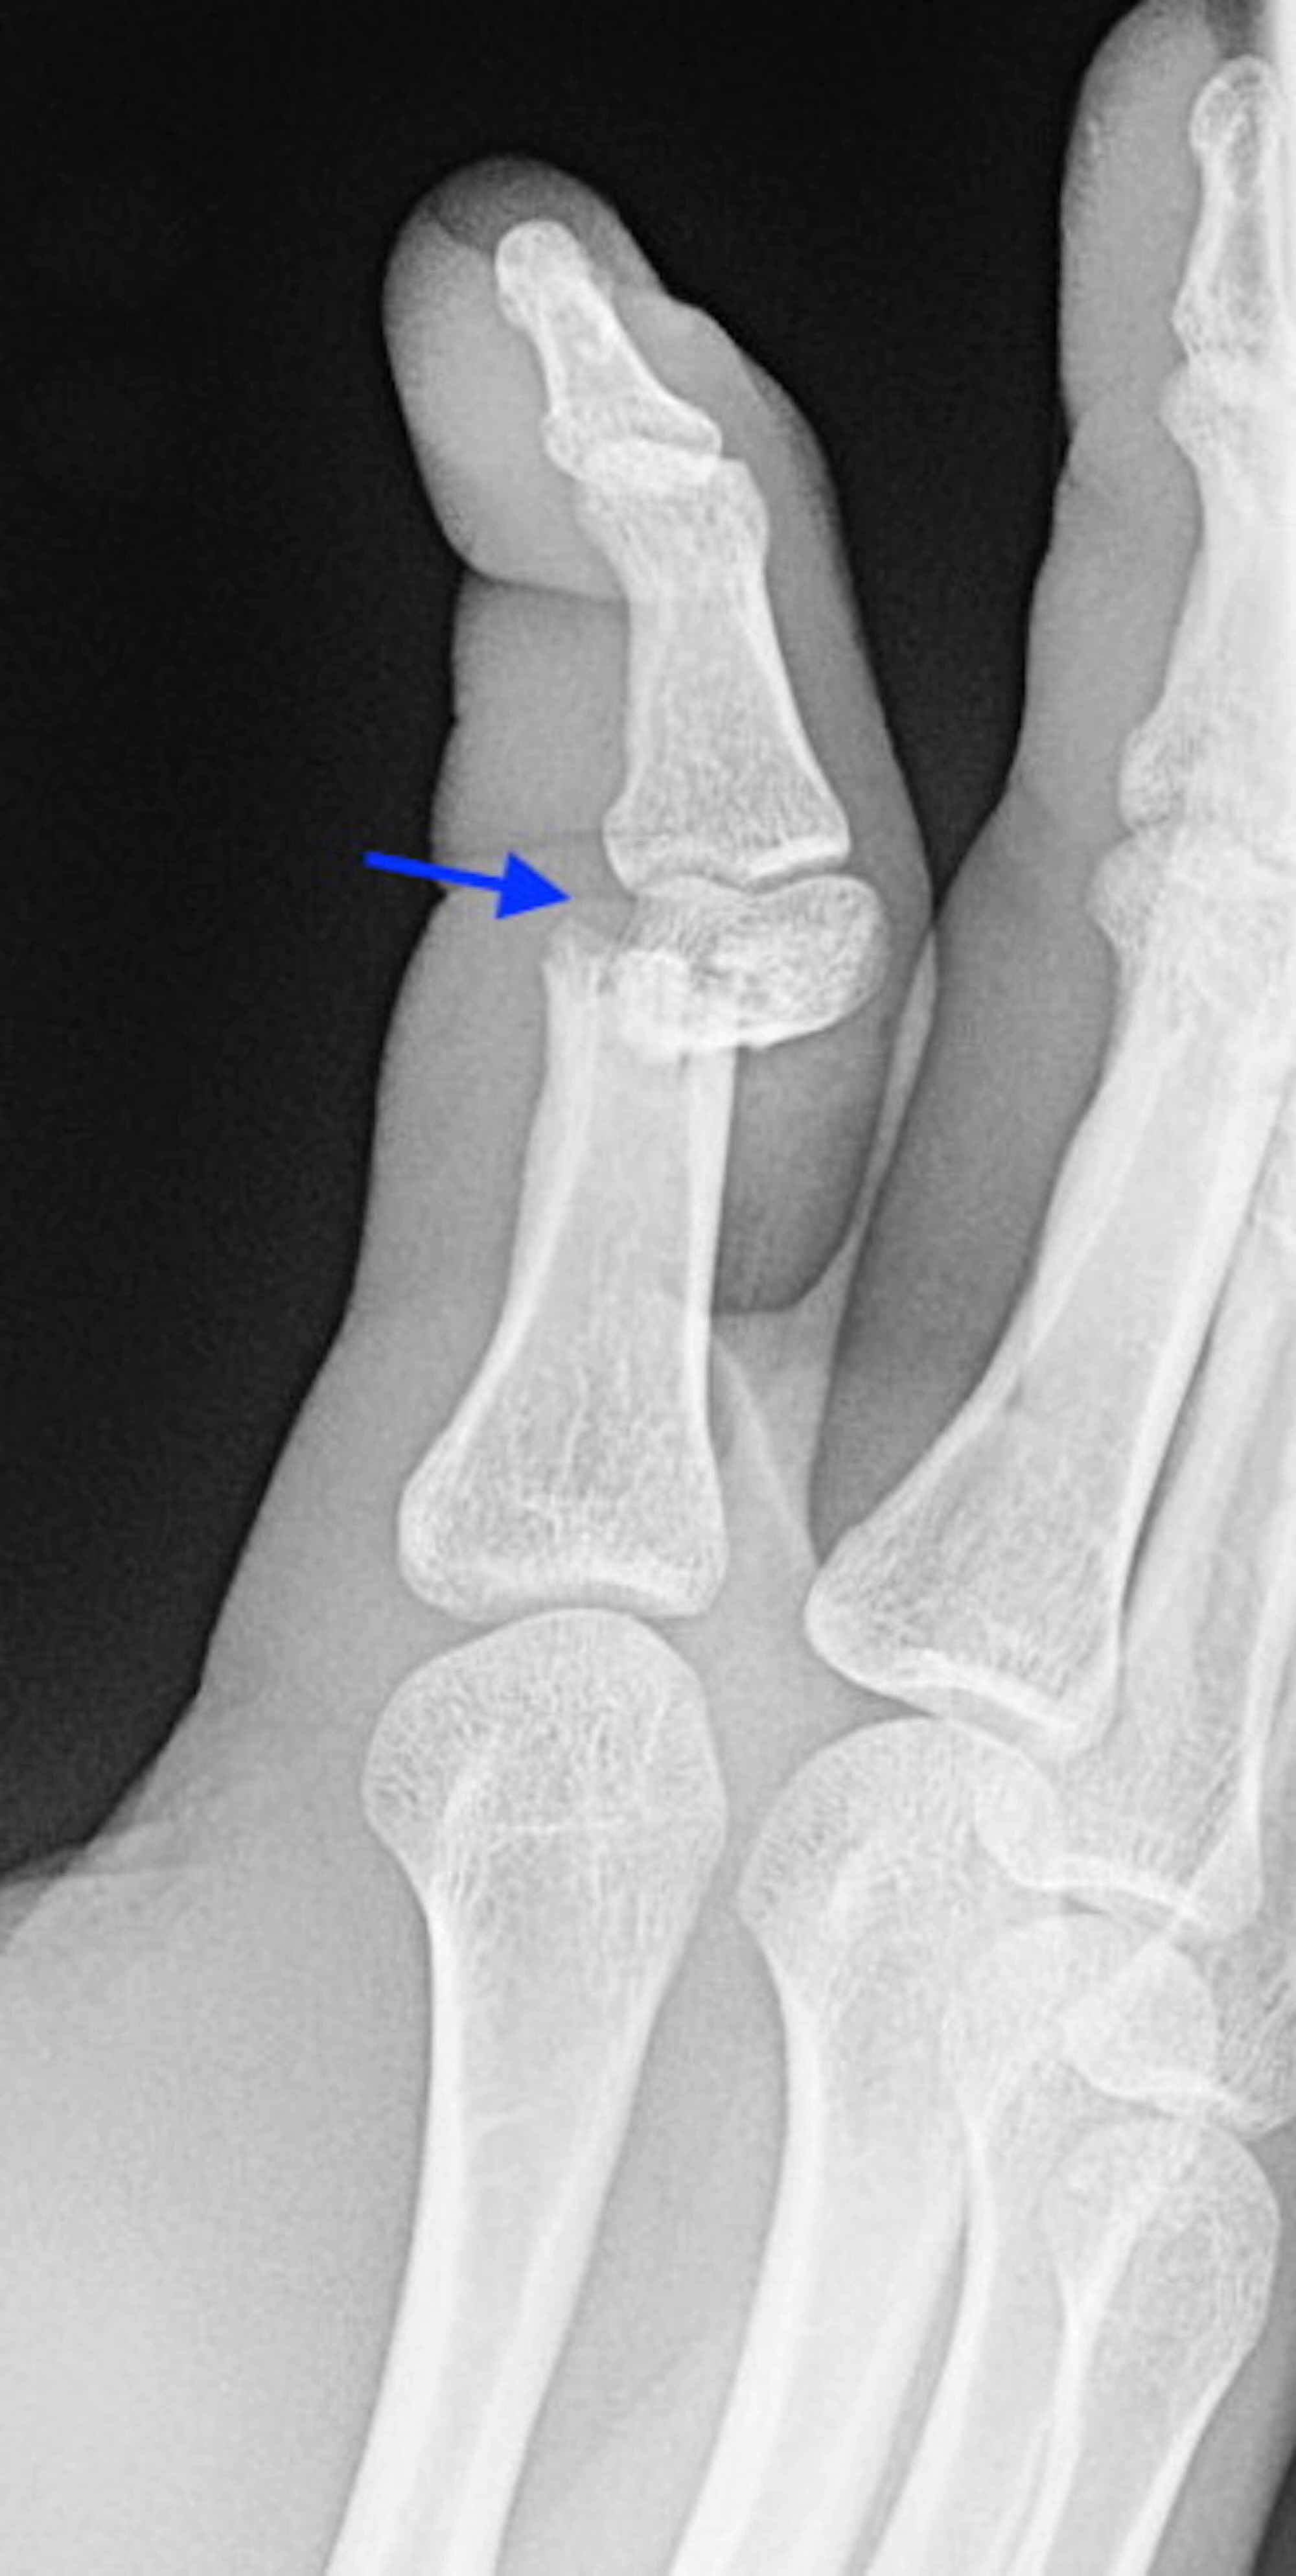

Avulsion Fracture Finger vrogue.co Compression Fracture Finger Treatment A broken hand can be caused by a fall, crush injury, or twisting injury, or through direct contact in sports. Diagnosis can be confirmed with. If you suspect you have a finger fracture, seek treatment as soon as possible. In many cases, a hand fracture will heal well with nonsurgical treatment. The aims of treatment of hand fractures should be. Compression Fracture Finger Treatment.